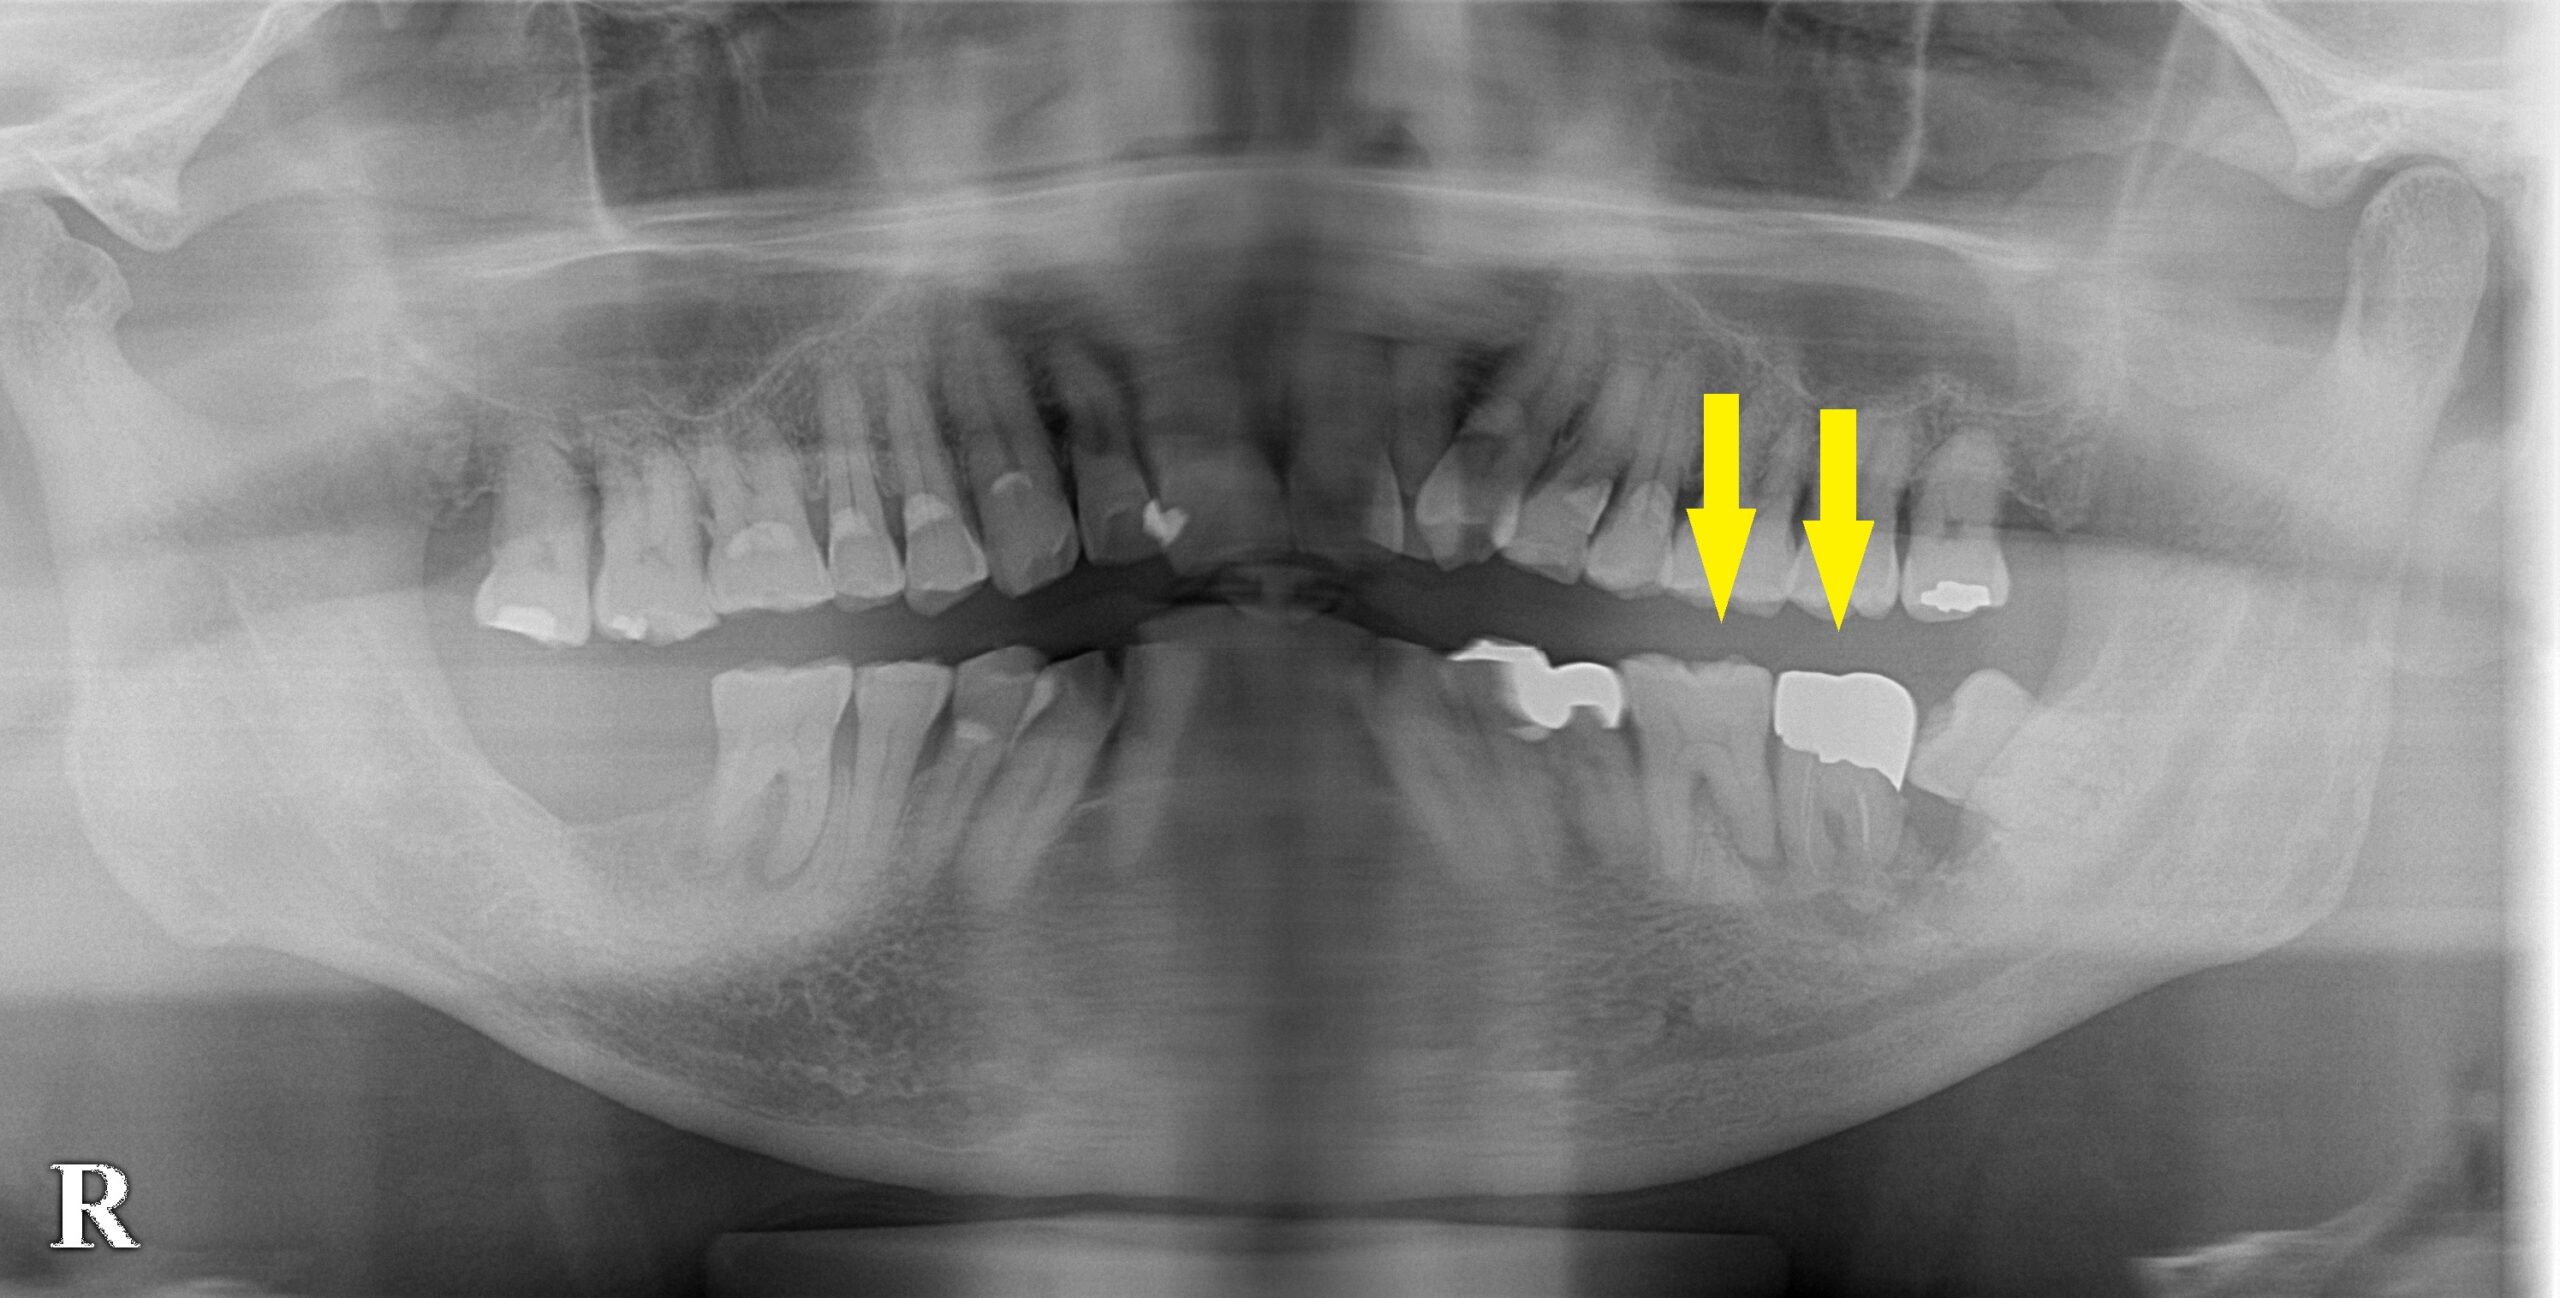

患者様は名古屋在住の70代男性。

左下顎の大臼歯が炎症を繰り返し、周囲の骨が大きく吸収されて、グラグラして痛いので、抜歯してインプラントにしたいとのご希望で来院されました。

3か月ほどして、CTを撮影してみると、下の写真2段目のように、大きく骨欠損となっていました。

2本のインプラント埋入を目指したいのですが、2本目の部位では、下方に通っている神経までの距離は3~4mm程度でした。